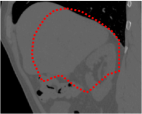

An example of CT/CBCT and MR/CBCT registration results are shown in figures 3 and 4, respectively. For both cases, the CBCT image (first column) was acquired intra-operatively after needle insertions and was employed as a reference for image registration. The pre-operative image is displayed before registration (second column), after PM-EA (third column) and after PM-EA+Evo (fourth column). The occurrence of patch shifts is reported for each spatial direction in panels (m–o): for each histogram, the shift with maximal occurrence is shown by the red dashed line. For panels (a–l), a ROI — manually defined on the CBCT image/encompassing the liver — is shown using red dash lines. Our visualization shows an improved correspondence of the contour of the liver with the manually defined liver boundary when the PM-EA solution is employed (see 3(c,g,k) and 4(c,g,k)). Moreover, an even better correspondence of the contour is observable using the PM-EA+Evo solution (see 3(d,h,l) and 4(d,h,l)).

Trans.

[X-Y]

CBCT

(a)

CT / No registration

(b)

CT / PM-EA

(c)

CT / PM-EA+Evo

(d)

Sag.

[X-Z]

(e)

(f)

(g)

(h)

Cor.

[Y-Z]

(i)

(j)

(k)

(l)

(m)

(n)

(o)